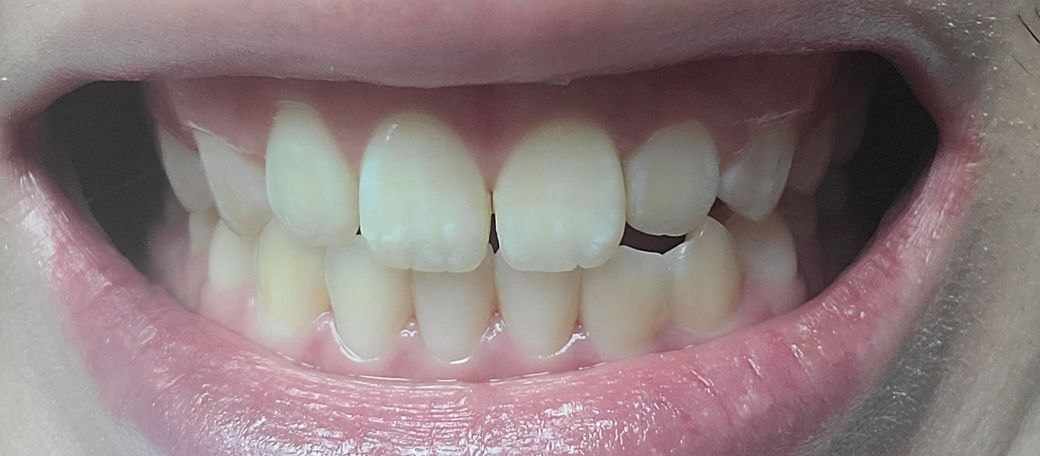

송곳니랑 그부근 어금니가 좀 더 틀어져서 깊게?물려요 턱이 비대칭이있긴한데 이정도비대칭은 사람마다 있다고들 하는데

-한쪽 송곳니은 살짝 떠있고 반대쪽은 잘물려요

왜 그런건지 모르겠어요 중심선이 안 맞아서 그런 건가요?

앞니 옆쪽 치아하나도 위아래가 부딪힙니다

아래사진은 일부러 중심선맞춰서 찍은사진입니다